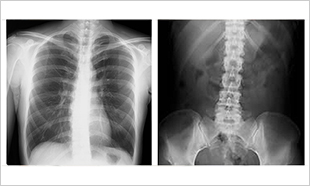

レントゲン検査

胸部や腹部をはじめ、頭の先から足の先までのあらゆる部位のX線撮影を行います。X線撮影に対して放射線被ばくのことが気にかかると思われますが、撮影に関しては大変少ない線量を用いています。撮影による身体への影響はほとんどありません。ただし、妊娠中、妊娠の可能性がある方は検査の前に必ずお申し出ください。